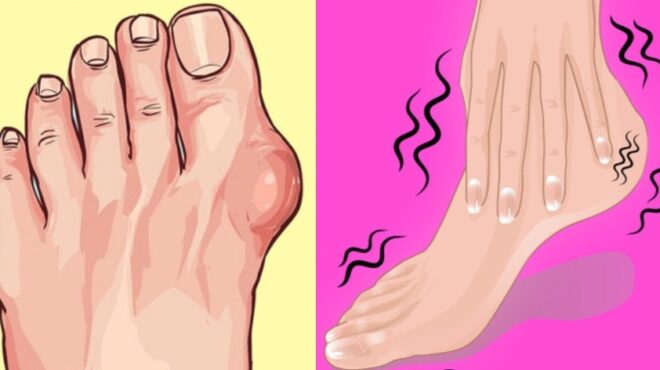

Προβλήματα στα πόδια: Κρύα πόδια, ζεστή καρδιά;

Εάν τα πόδια σας είναι διαρκώς κρύα μπορεί να είναι αποτέλεσμα κακής κυκλοφορίας του αίματος. Η κακή κυκλοφορία πολλές φορές σχετίζεται με το κάπνισμα, την υψηλή αρτηριακή πίεση ή τα καρδιακά προβλήματα.

Η νευρική βλάβη του μη ελεγχόμενου διαβήτη μπορεί επίσης να προκαλεί κρύα αίσθηση στα πόδια. Άλλα πιθανά αίτια είναι ο υποθυρεοειδισμός και η αναιμία. Συμβουλευτείτε τον γιατρό σας ώστε να εντοπίσετε οποιοδήποτε τυχόν υποβόσκον πρόβλημα.

Προβλήματα στα πόδια: Άσπρα, κόκκινα, μπλε δάχτυλα

Αν πάσχετε από το σύνδρομο Raynard μπορεί να παρατηρήσετε τα δάχτυλά σας να αλλάζουν απόχρωση από φυσιολογική σε άσπρη, μετά σε μπλε , σε κόκκινη και να επανέρχονται πάλι στο φυσιολογικό. Αυτό οφείλεται στο ξαφνικό στένεμα των αρτηριών, μία κατάσταση που ονομάζεται αγγειοσπασμός. Το στρες ή οι αλλαγές στη θερμοκρασία μπορεί να πυροδοτήσουν τους αγγειοσπασμούς αυτούς, που συνήθως δεν οδηγούν σε άλλα προβλήματα υγείας. Το σύνδρομο αυτό μπορεί επίσης να συνδέεται με ρευματοειδή αρθρίτιδα, σύνδρομο Sjögren ή προβλήματα θυρεοειδούς.

Προβλήματα στα πόδια: Πληκτροδακτυλία

Στην πληκτροδακτυλία το σχήμα των δακτύλων των ποδιών (και συχνά και των χεριών) αλλάζει. Τα νύχια είναι πιο στρογγυλά στην κορυφή και καμπυλώνουν προς τα κάτω. Το πιο συχνό αίτιο της κατάστασης αυτής είναι η πάθηση των πνευμόνων αν και μπορεί να προκαλείται και από καρδιακές παθήσεις, ηπατικές και πεπτικές διαταραχές ή ορισμένες μολύνσεις. Κάποιες φορές η πληκτροδακτυλία εμφανίζεται ενδοοικογενειακά χωρίς να συντρέχει κάποια υποβόσκουσα ασθένεια.

Προβλήματα στα πόδια: Πρησμένα πόδια

Συνήθως πρόκειται για μία προσωρινή ενόχληση που προκαλείται από την ορθοστασία ή την ακινησία, όπως σε περιπτώσεις μεγάλων πτήσεων, και κυρίως στις εγκυμονούσες. Αντιθέτως, όταν το πρήξιμο των ποδιών δεν υποχωρεί ίσως είναι σημάδι μία σοβαρής ιατρικής κατάστασης. Το επίμονο πρήξιμο των ποδιών μπορεί να οφείλεται σε κακή κυκλοφορία του αίματος, σε προβλήματα στο λεμφικό σύστημα ή στην ύπαρξη θρόμβου. Άλλοι παράγοντες είναι οι νεφρικές διαταραχές ή η υπολειτουργία του θυρεοειδούς. Αν παρατηρήσετε επίμονο πρήξιμο των ποδιών σας συμβουλευτείτε τον γιατρό σας.

Προβλήματα στα πόδια: Κάψιμο

Η αίσθηση καψίματος στα πόδια είναι συνηθισμένη στους διαβητικούς με περιφερειακή νευρική βλάβη. Μπορεί επίσης να προκληθεί από ανεπάρκεια Βιταμίνης Β, από το «πόδι του αθλητή», από χρόνιες νεφρικές παθήσεις, από κακή κυκλοφορία στα πόδια (περιφερειακές αρτηριακές παθήσεις) ή από υποθυρεοειδισμό.